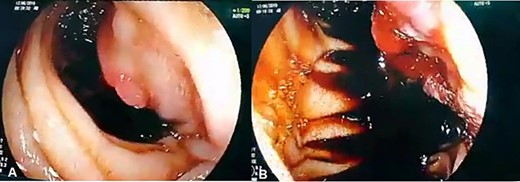

Admission work-up revealed anemia (hemoglobin = 7.8 g/dL, hematocrit = 23%). Emergent upper GI endoscopy showed active bleeding of ulcerated tumor on the third duodenal portion (Fig. 1A and B). Enhanced computed tomography (CT) scan revealed 5 × 4.5 cm hypervascular mass on the previous duodenojejunal anastomosis without metastasis (Fig. 2A and B). Diagnosis of locally recurrent duodenal GIST was suspected. Progressive anemia had developed in spite of transfusion 3 units packed red blood cells, and thus, emergent laparotomy was performed. During laparotomy, we found recurrent mass just on the previous duodenojejunal anastomosis without intraperitoneal or liver implantations (Fig. 3). A careful limited resection of the distal third part of the duodenum with proximal jejunum was carried out (Fig. 4). Side-to-side anastomosis between the second duodenal portion and jejunum was performed (Fig. 5A–C). Feeding jejunostomy tube was inserted. Post-operative course was uneventful. The patient was discharged on the ninth post-operative day. Histopathology report revealed 4 × 3 cm spindle cell type duodenal GIST, mitotic index < 5/50HPF, resection margins free more than 5 mm, intact pseudocapsule with vascular invasion and tumor emboli (Fig. 6A and B). Immunohistochemical staining for CD117 was positive (Fig. 6C). Unfortunately, molecular assessment of the recurrent tumor was unavailable in our institute. Adjuvant imatinib 400 mg/day was administered. To detect any recurrence in the liver or peritoneal cavity during adjuvant imatinib therapy, intensive surveillance with enhanced abdomen and pelvis CT scan every 6 months was recommended [3].

(A, B) Upper GI endoscopy shows centrally ulcerated recurrent tumor in the third portion of the duodenum with active bleeding.